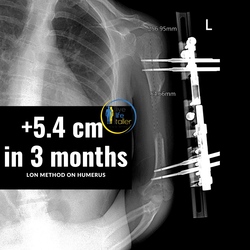

With the combined method (Lon method), an internal nail and an external fixation are attached which allow the bone to be extended from the outside.